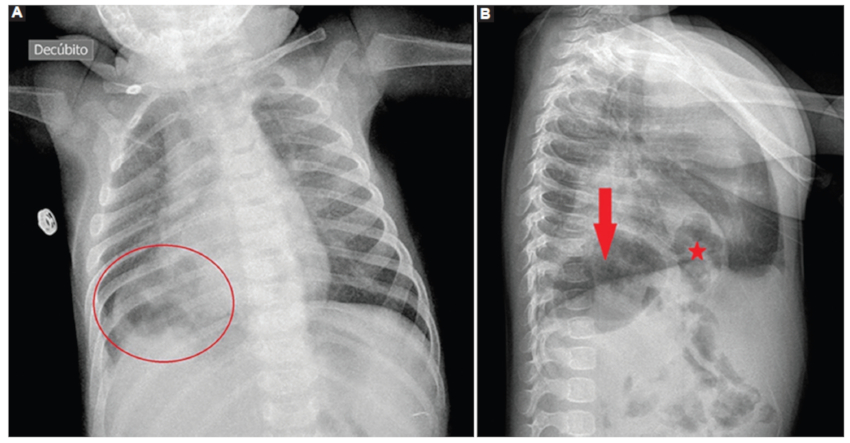

Reconsultó tras 20 días por reaparición de vómitos hemáticos y pérdida ponderal. En la exploración física destacó una hipoventilación en base pulmonar derecha, sin signos de dificultad respiratoria y afebril, con analítica sanguínea anodina. Se realizó una radiografía de tórax, objetivando una imagen en base pulmonar derecha compatible con hernia diafragmática (Fig. 1), hallazgo que permitió la realización de pruebas confirmatorias (Figs. 2 y 3) y un manejo precoz y adecuado del caso.

De manera posnatal, el hallazgo más frecuente es observar aire retrocardiaco o la presencia de la sonda nasogástrica intratorácica en una radiografía de tórax9.